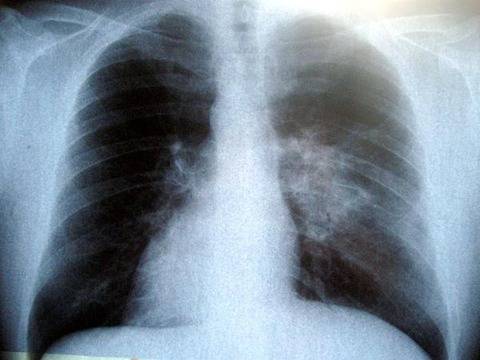

Туберкулозата е хронично инфекциозно заболяване, което в 90 % от случаите засяга белодробната система, а в 10% – и други органи и системи (централна нервна система, сърце, очи, кожа, органи на коремната кухина, кости и стави, уро-генитална система и други).

Причинителят на туберкулозата е Микобактериум туберкулозис (бактерий на Кох), който се отличава със значителна устойчивост във външната среда. Повечето от хората, които се заразяват с туберкулозните бактерии, успяват да се «преборят» с тях и да спрат растежа им – бактериите остават да живеят в тялото на заразения човек, но не са активни. След време може да се активират от само себе си. Това състояние се нарича скрита туберкулозна инфекция – хората със скрита инфекция нямат определените за заболяването симптоми и не могат да заразяват други хора.

Източници на зараза могат да бъдат болните от туберкулоза хора и животни (главно едър рогат добитък, по-рядко свине, птици и други), както и техните продукти.Проникването на инфекцията най-често става през дихателните пътища. При кашлица, кихане, разговор болният отделя туберкулозните бактерии във въздуха. От пръските при кашляне и храчене хората, които се намират в близост, могат да се заразят непосредствено по въздушно-капков път. В храчките на болните се съдържат милиони бактерии. Заразата може да се пренeсе и чрез праха в стаите и по улиците, където туберкулозните бактерии остават дълго време жизнеспособни.

СИМПТОМИ НА БЕЛОДРОБНАТА ФОРМА НА ЗАБОЛЯВАНЕТО

► Кашлица, която може да продължи седмици, като в началото се наблюдава леко покашляне, а при напредване на болестния процес кашлицата се засилва и става влажна;

► Храчене – болните отделят храчки главно сутрин, понякога примесени с кръв;

► Повишена температура – болните имат повишена температура за продължителен период от време (дори с месеци). Възможно е заболяването да протече и без повишена температура;

► Изпотяване – то е обилно, особено нощно време;

► Болки в гръдния кош – те се срещат при повечето болни между плешките, в раменните и страничните области на гръдния кош, като се засилват при дишане и кашлица;

► Безапетитие – то води до намаляване на телесното тегло;

► Задух – този признак е характерен за напредналите стадии на болестта;

► Отпадналост и безсилие – тези симптоми продължават дълго време.

Туберкулозата може да протече и напълно безсимптомно в около 15% от случаите. При възрастни хора често наподобява пневмония или друго инфекциозно заболяване.